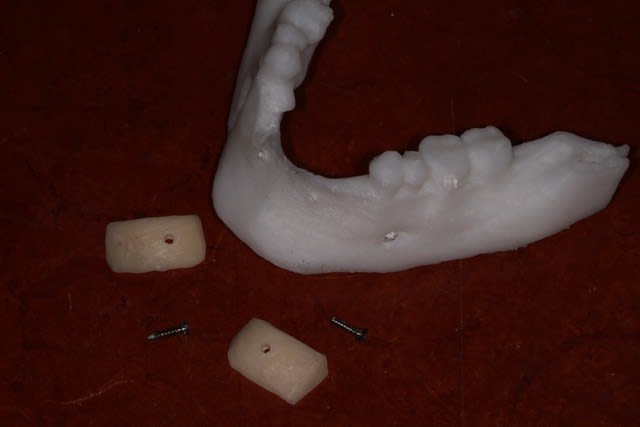

Voici 3 possibilités traité sur la maquette mandibulaire.

2 blocs biobank 20x10 :700 € + membrane et vis

Coffrage avec prélèvement ramique : biomateriaux + vis , de la membrane et de la sueur .

Coffrage avec membrane en PDLLA 126x11x0,8mm :300 € ttc + biomatériaux ( autogene + minéros, c'est pas mal ) + vis d'espacement et de fixation + membrane collagene ( http://www.biagginimedical.com/#!sonicweldrx/civk )

L'étude me fait éliminer le coffrage ramique, car je me retrouve avec une assez faible épaisseur au niveau de 32 42, ( sans parler de la difficulté du prélèvement, vu le peu d'os disponible ).

Reste les blocs, et un coffrage en adaptant la technique sonicweldrx en fixant la membrane PDLLA avec des vis d'ostéosynthèse.

j'avais cru voir dans un kit de vis, des vis d'espacement avec une minivis dans la tête, pour fixer la membrane , mais je ne sais pas si j'ai rêvé, je ne retrouve pas le site web correspondant ( voir mon schéma )

Bravo pour les maquettes, très beau travail de réflexion!

Je pour la forme, faut 2 vis par bloc, sinon ça bouge...